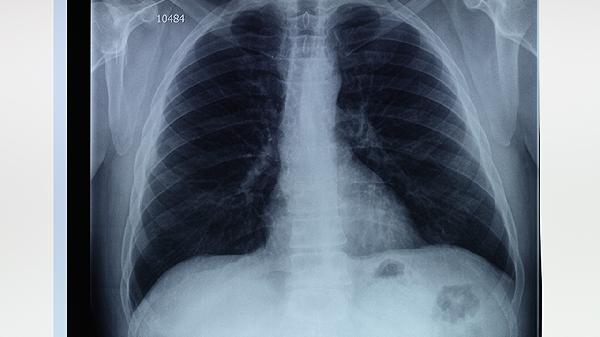

术后1个月、3个月、6个月分别复查胸部CT,评估粘连变化情况。出现胸闷加重、血氧饱和度下降时需及时就诊。复查内容包括肺功能测试、胸部影像学检查等,必要时进行支气管镜检查。